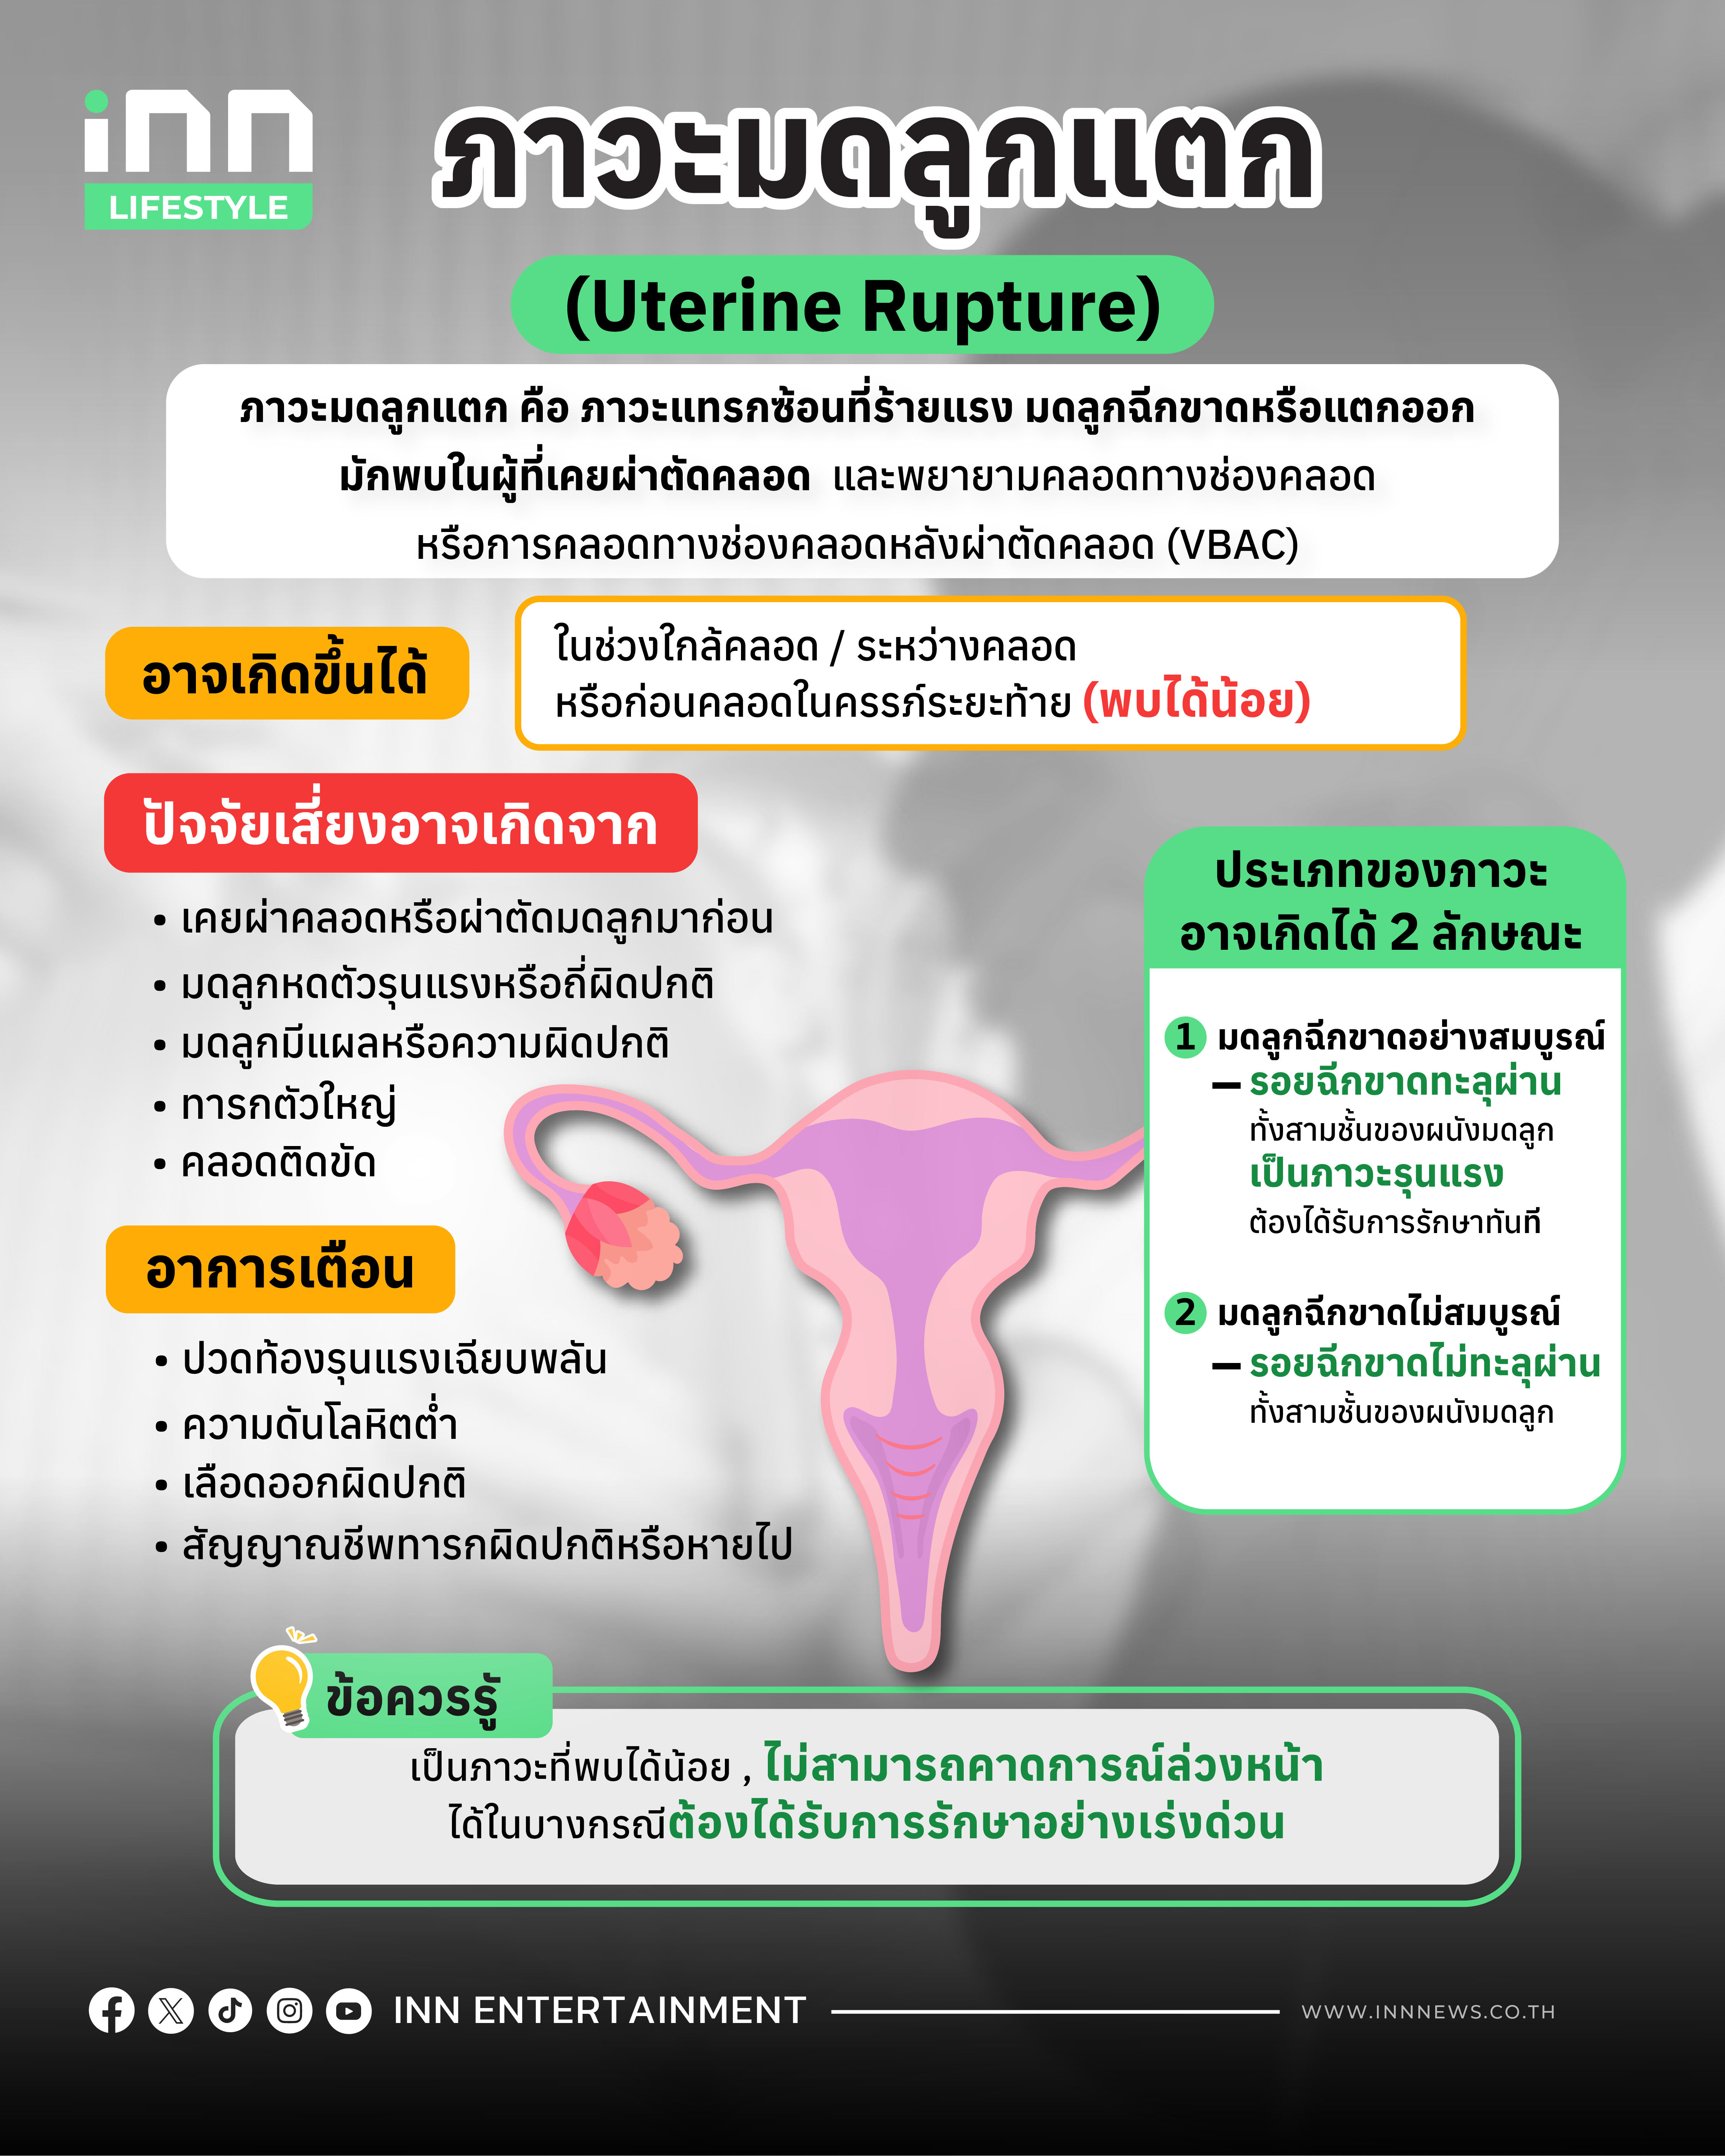

มดลูกแตก (Uterine Rupture) คือภาวะที่ผนังมดลูกฉีกขาดทะลุทุกชั้น ส่งผลให้โครงสร้างของมดลูกไม่สมบูรณ์ ทำให้ทารก เลือด หรือรก มีโอกาสหลุดออกนอกโพรงมดลูก เป็นภาวะฉุกเฉิน ถ้าหากปล่อยทิ้งไว้โดยไม่รับการรักษาอย่างเร่งด่วน อาจก่อให้เกิดการเสียเลือดรุนแรง เสี่ยงทั้งต่อแม่และเด็กในครรภ์เป็นอย่างมาก

มดลูกแตก เกิดขึ้นได้จากสาเหตุต่าง ๆ ไม่ว่าจะเป็น

- การใช้ยากระตุ้นการบีบตัวของมดลูก: การใช้ยากระตุ้นการคลอด ถ้าหากได้รับในปริมาณที่ไม่เหมาะสม มากเกินไป หรือน้อยเกินไป อาจส่งผลให้มดลูกบีบตัวแรง จนผนังมดลูกรับแรงกระแทกมากเกินไป ซึ่งเสี่ยงต่อภาวะมดลูกแตกได้

- มดลูกขยายตัว: มดลูกที่ขยายตัวผิดปกติ จากการตั้งครรภ์แฝด หรือทารกที่ตัวใหญ่ อาจทำให้ผนังมดลูกตึง หรือฉีกขาดได้

- ความผิดปกติของมดลูกที่มีอยู่เดิม: ในบางกรณี ผู้หญิงบางคนอาจมีความผิดปกติของมดลูกอยู่แล้วแต่ไม่รู้ตัว เช่น มดลูกมีขนาดเล็ก หรือรูปร่างผิดปกติ เมื่อเกิดการตั้งครรภ์ มดลูกจึงไม่สามารถขยายตัวได้ตามปกติ และเพิ่มความเสี่ยงต่อการฉีกขาด

- มดลูกได้รับแรงกระแทกรุนแรง: กรณีที่เคยประสบอุบัติเหตุรุนแรง อาจส่งผลกระทบต่อมดลูก จนทำให้เสี่ยงต่อภาวะมดลูกแตกได้

- การคลอดติดขัด: กรณีที่การคลอดติดขัด หรือใช้เวลาคลอดนานกว่าปกติ ก็เป็นอีกหนึ่งสาเหตุที่ทำให้เสี่ยงต่อภาวะมดลูกแตกได้

มดลูกแตก ถือเป็นภาวะที่ไม่ได้พบบ่อยนัก แต่ส่วนใหญ่จะพบใน “คุณแม่ที่เคยผ่าคลอดมาก่อน” โดยเฉพาะผู้ที่เคยผ่าตัดคลอดในการตั้งครรภ์ครั้งก่อน และมีแผลผ่าตัดแนวตั้งที่มดลูก, ผู้ที่คลอดทางช่องคลอดหลังจากมีประวัติผ่าตัดคลอดมาก่อน รวมถึงผู้ที่ได้รับยากระตุ้นการคลอด หรือผู้ที่ตั้งครรภ์หลายครั้งมาก

นอกเหนือจากนี้ ก็อาจสามารถเกิดขึ้นได้จากปัจจัยอื่น เช่น การใช้ยาเร่งคลอดปริมาณมากหรือนานเกินไป, เคยขูดมดลูก หรือผ่าตัดเนื้องอกมดลูก ,เกิดอุบัติเหตุกระแทกหน้าท้องอย่างรุนแรง หรือมดลูกขยายตัวมากเกินไป จากการตั้งครรภ์แฝด หรือทารกที่ตัวใหญ่มาก เป็นต้น

สำหรับอาการหรือสัญญาณเตือนภาวะมดลูกแตก จะแตกต่างกันออกไปขึ้นอยู่กับแต่ละคน แต่โดยทั่วไปจะมีสัญญาณที่สังเกตได้ ดังนี้

- ปวดท้องรุนแรง และปวดตลอดเวลา เหมือนกับมีอะไร “ฉีกขาด” ในช่องท้อง

- มดลูกหดรัดตัวผิดจังหวะ หรือหยุดหดรัดตัวกะทันหัน

- อ่อนเพลีย หน้ามืด ใจสั่น

- เลือดออกทางช่องคลอดมากกว่าปกติ

- กรณีตั้งครรภ์อยู่ การเต้นหัวใจของทารกอาจผิดปกติ